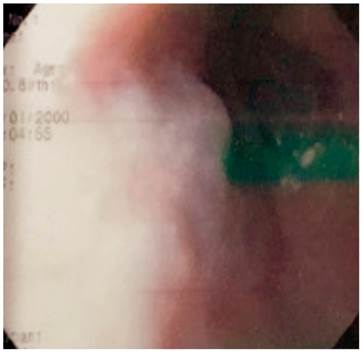

Paciente AMDA: mujer de 73 años con diagnóstico clínico de RGE, con antecedente de EPOC por exposición al humo de leña, uso permanente de inhaladores y oxígeno suplementario en casa. En el momento del examen físico se presenta con obesidad, cianosis de piel y mucosas y abotagamiento (Figura 2). En la EGD, se encontraron várices en los 6 primeros centímetros del esófago (Figura 3) con ausencia distal de estas (Figura 4), sin estigmas de sangrado o de riesgo y gastritis crónica superficial.